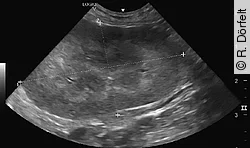

Eine Röntgenuntersuchung des Abdomens in 2 Ebenen kann zum Ausschluss anderer Ursachen der Azotämie, wie z. B. Uretersteinen, sinnvoll sein. Die Ultraschalluntersuchung der Niere sollte bei jeder Katze mit Verdacht auf eine Nierenerkrankung erfolgen. Bei der akuten Nierenschädigung sind die Nieren oft vergrößert, zudem ist die Nierenrinde häufig hyperechogen. Falls kleine Nieren und eine höckerige Oberfläche vorhanden sind, ist dies eher ein Hinweis auf eine chronische Nierenerkrankung.